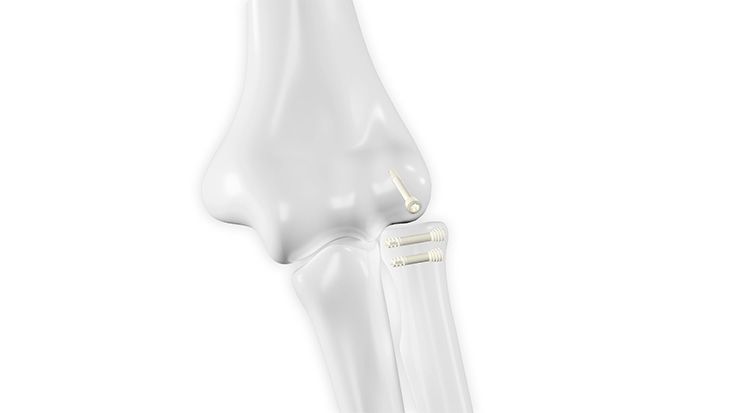

Implantate | Fuß

HBS 2 Resorb Mg und mm.CS

Nach über 100.000 erfolgreichen HBS- und HBS 2-Implantationen weltweit startet eine neue Ära mit der Erweiterung des Angebots um HBS 2 Resorb Mg Kompressionsschrauben. Diese innovative Schraube aus einer speziellen Magnesiumlegierung behält die bewährte HBS 2-Geometrie bei und ist nun zudem bioabsorbierbar. Auf diese Weise bleibt dem Patienten eine zweite Operation zur Metallentfernung erspart.

Magnesiumimplantate durchlaufen im Körper einen kontrollierten Abbauprozess, bei dem das Implantat in Knochen umgewandelt wird und Wasserstoffgas freigesetzt wird. Eine spezielle Oberflächenumwandlung verlangsamt die Korrosion des Implantats, wodurch die Abbaurate vermindert wird, was entscheidend für die Frakturheilung und die Integration des Implantats in das Knochengewebe ist.

Unser resorbierbares Schraubenportfolio, bestehend aus HBS 2 Resorb und mm.CS Implantaten unseres Kooperationspartners medical magnesium enthält kanülierte, kopflose Kompressionsschrauben in fünf verschiedenen Durchmessern. Dies ermöglicht den Einsatz in einem weiten Indikationsspektrum. Alle Schrauben sind selbstschneidend und können mit den bekannten und bewährten Operationstechniken eingesetzt werden. Lediglich das Kopfraumfräsen wird als zusätzlicher Operationsschritt ergänzt, um das Eindrehmoment beim Implantieren zu reduzieren.